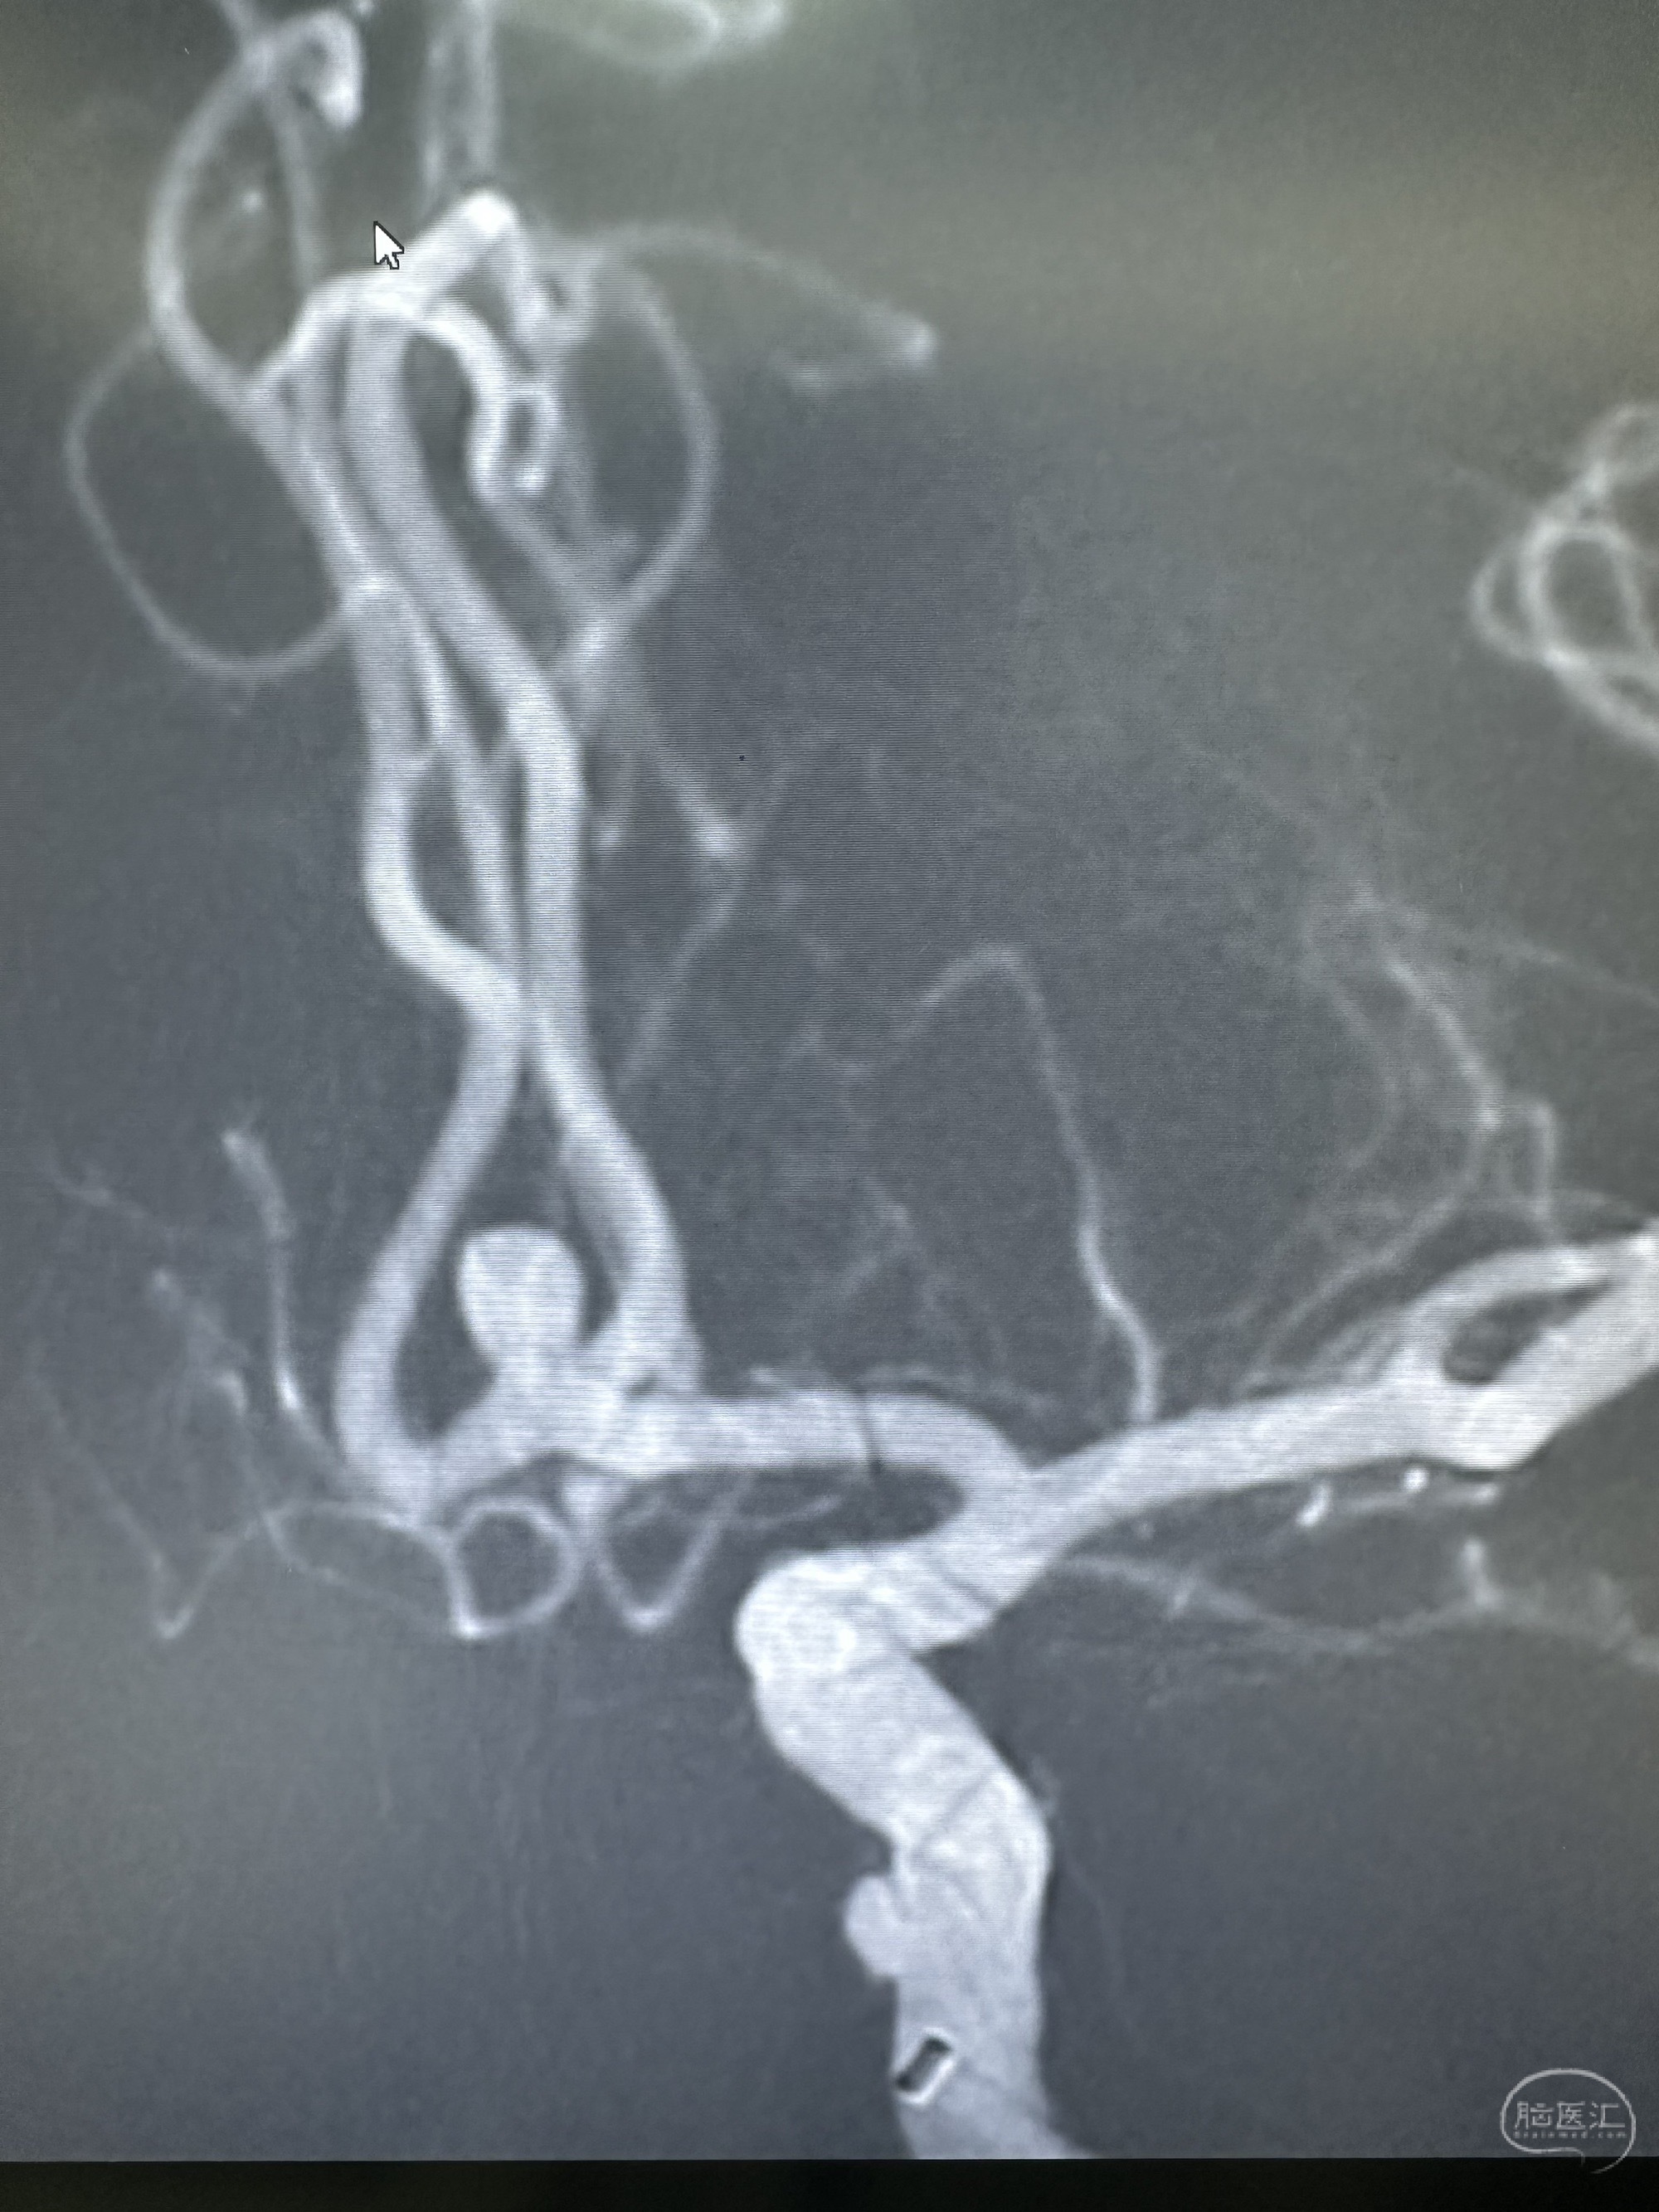

3D造影